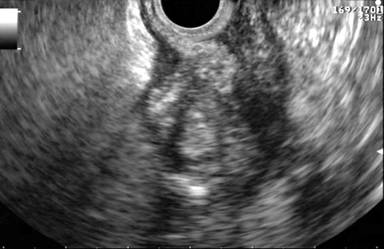

A 38-year-old male patient presented to the emergency room due to acute epigastric pain, nausea and vomiting. Physical examination revealed tenderness in the upper abdomen. Body temperature was 37.3°C. C-reactive protein was 113 mg/L (reference range: 0-3 mg/L) and his white blood cell count was raised (15.5 x109/L; reference range: 3.5-8.8 x109/L). Renal and liver function tests and serum pancreatic amylase were normal. He was otherwise healthy and was not taking any medications. Upper gastrointestinal endoscopy showed a subepithelial lesion in the gastric antrum (Figure 1). Abdominal computed tomography scan revealed a heterogeneous 4 cm malignant-looking lesion in the gastric antrum with suspected invasion of the perigastric fat (Figure 2). Endoscopic ultrasound (EUS) confirmed the presence of a subepithelial lesion in the antrum, that had heterogeneous appearance and involved all subepithelial layers of the gastric wall (Figure 3). An EUS-led fine needle aspiration (FNA) showed inflammatory cells only. The patient recovered symptomatically and blood tests normalized within 5 days. However, on the grounds of the imaging findings, malignancy could not be excluded and distal gastrectomy was performed. Histopathology of the surgical specimen confirmed the presence of ectopic pancreas in the gastric antrum (Figure 4a) but showed no cancer. However, there was both chronic and acute inflammation with neutrophil infiltration (Figure 4b). Twelve months following surgery he was asymptomatic.

Figure 3. EUS showed a heterogeneous lesion involving all layers of the gastric wall (beyond the mucosal layer). |